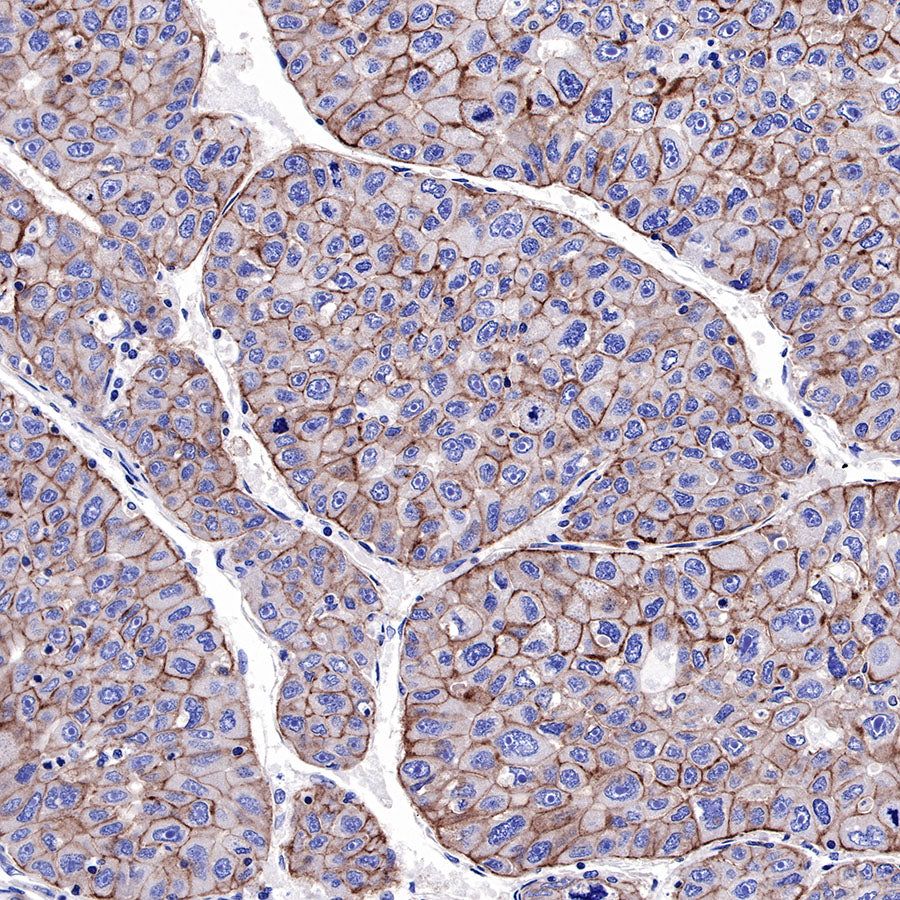

IHC shows positive staining in paraffin-embedded human lung adenocarcinoma. Anti-EGFR antibody was used at 1/2000 dilution, followed by a HRP Polymer for Mouse & Rabbit IgG (ready to use). Counterstained with hematoxylin. Heat mediated antigen retrieval with Tris/EDTA buffer pH9.0 was performed before commencing with IHC staining protocol.

IHC shows positive staining in paraffin-embedded human hepatocellular carcinoma. Anti-EGFR antibody was used at 1/2000 dilution, followed by a HRP Polymer for Mouse & Rabbit IgG (ready to use). Counterstained with hematoxylin. Heat mediated antigen retrieval with Tris/EDTA buffer pH9.0 was performed before commencing with IHC staining protocol.

IHC shows positive staining in paraffin-embedded mouse colon. Anti-EGFR antibody was used at 1/500 dilution, followed by a HRP Polymer for Mouse & Rabbit IgG (ready to use). Counterstained with hematoxylin. Heat mediated antigen retrieval with Tris/EDTA buffer pH9.0 was performed before commencing with IHC staining protocol.

IHC shows positive staining in paraffin-embedded rat stomach. Anti-EGFR antibody was used at 1/500 dilution, followed by a HRP Polymer for Mouse & Rabbit IgG (ready to use). Counterstained with hematoxylin. Heat mediated antigen retrieval with Tris/EDTA buffer pH9.0 was performed before commencing with IHC staining protocol.